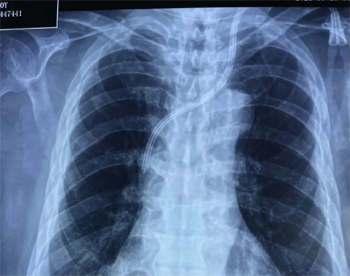

入院当天,在肾内科副主任、张东亮主任医师的带领下,肾内科血管通路组成员(付晨主治医师)、病房组长(史丹主治医师)、及陈天怡住院医师共同参与这次感染导管拔除及对侧颈内静脉导管植入术。在清洁区域切开、分离并截断导管后,进行皮下隧道内清创,由导管末端直接取出感染导管;同时B超探查显示患者右侧颈内静脉纤细,直径仅2mm,考虑原位插管困难。但如选择对侧(左侧)颈内静脉置管,则风险极高:正常解剖左侧颈内静脉即有两个近直角转弯,置管过程极易造成静脉损伤、纵隔损伤以及血胸气胸等严重并发症,何况老人的颈部病变及解剖结构无疑更进一步极大增加了手术风险。张东亮主任医师凭借多年丰富的经验,结合老人综合情况,选择了这个风险虽高但远期获益明显的手术入路。为保障手术的顺利进行、保障患者安全及有效治疗,科室团队积极协调超声、CRRT机、床旁X线,积极准备应急预案。

成功插入左颈内静脉肾透析用带CUFF半永久导管